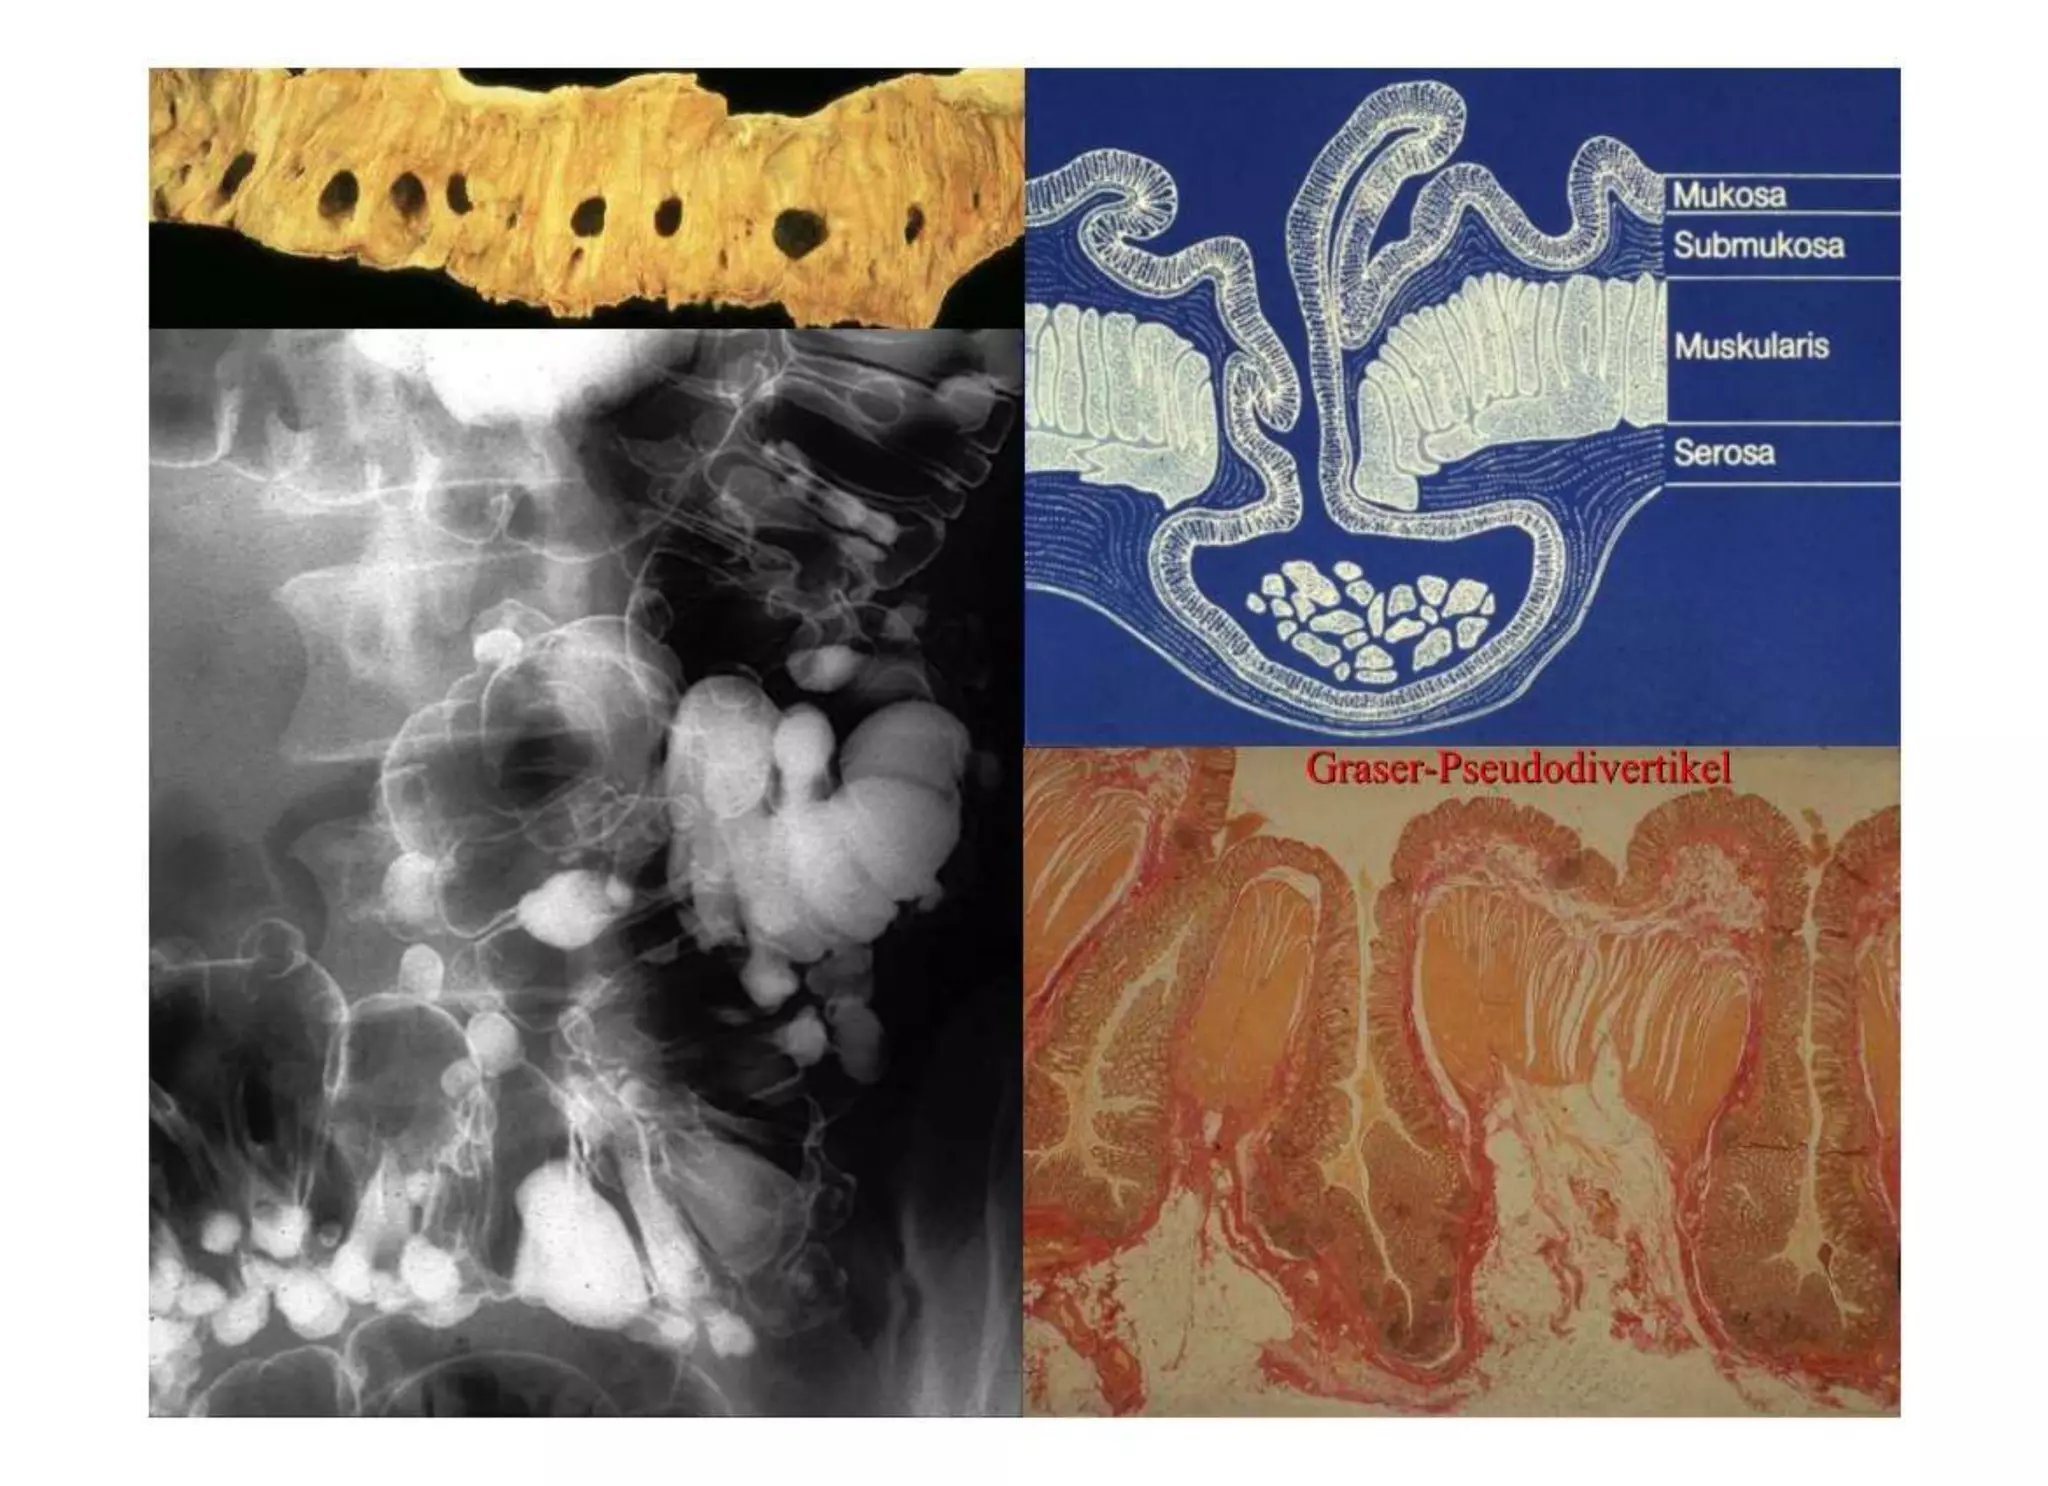

Chronische Enteropathie und Ileus, Dünndarm und Dickdarmdiagnostik, Mechanischer und paralytischer Ileus, Eingeklemmte Darmabschnitte, aufgereihter Bridenileus, und dazu Dickdarmileus, eingeklemmte Hernien, Weitergabeskript